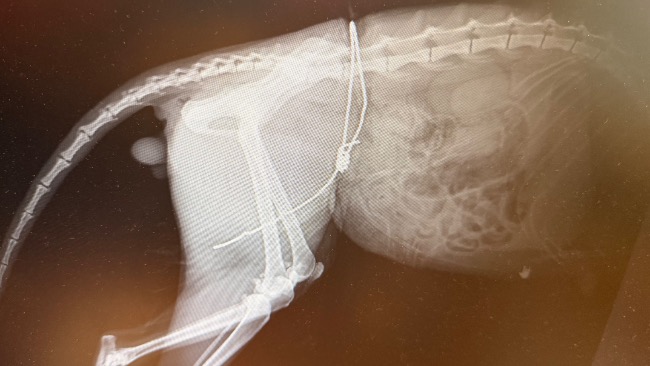

Ofiara kłusownika. Wokół jego ciała zaciśnięty, wrośnięty wnyk. Metal wrósł w ciało, rozrywając skórę i mięśnie. Każdy ruch oznaczał ból nie do opisania. Boguś błagał o ratunek, choć nikt go nie słyszał.

Rana obejmuje niemal 25 procent ciała. To nie jest zwykłe zranienie. To potworne okaleczenie, długotrwałe cierpienie, stan zapalny, ryzyko sepsy i śmierci. Ból ciągły, bez chwili ulgi. Niewyobrażalne cierpienie zadane przez człowieka.

Dziś walczy o życie. Przed nim bardzo długa i trudna rekonwalescencja, specjalistyczne leczenie, operacje, opatrunki, rehabilitacja. Jego stan jest krytyczny, a każdy dzień to walka o przetrwanie.